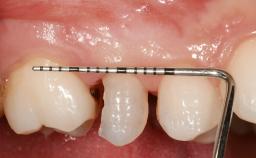

Early Placement of an Implant in a Maxillary Right Central Incisor Site

This 41-year-old female patient was referred to the clinic for the replacement of the right central incisor, since the tooth had developed a root fracture in the long axis that made extraction necessary. The healthy, non-smoking patient was first seen with the tooth still in place. A detailed Esthetic Risk Assessment was performed.The patient was worried about her dental esthetics and had high expectations for a successful treatment outcome from an esthetic point of view. The patient had a medium lip line that displayed parts of the gingiva in the anterior maxilla upon smile.

Bone Level at Adjacent Teeth <= 5 mm to contact point 5.5 to 6.5 mm to contact point > 7 mm to contact point

Width of Edentulous Span 1 tooth (>= 7 mm) 1 tooth (< 7 mm) 2 teeth or more

Mesio-Distal Space Symmetry +/- 1 mm of contra-lateral tooth